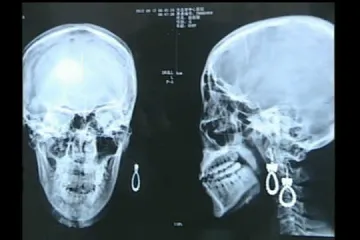

operiran je / Maleni Peruanac (2) progutao 8 medicinskih igala. Otkud mu? Majka mu radi na farmi, njima se cijepe životinje